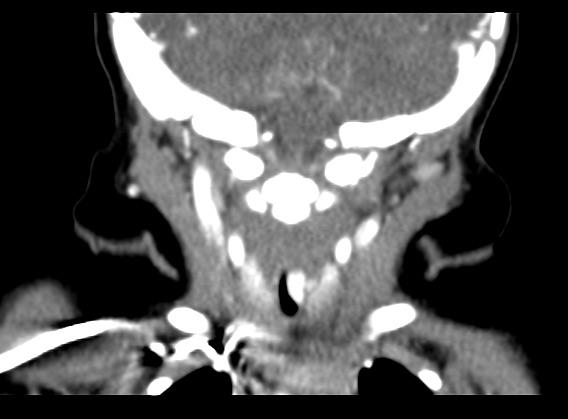

1.2诊断标准与方法对于可疑SGH患儿均需行纤维喉镜检查,声门下单侧或双侧局部隆起,表面光滑、暗红色,阻塞声门下气道,则高度怀疑SGH(图1)。颈部增强CT见声门下局部软组织增厚,气道变窄,增强扫描强化明显(图2a,b,c),诊断明确后给药。

颈部增强CT:左侧声门下局部软组织增厚,向气道内突起,强化明显。